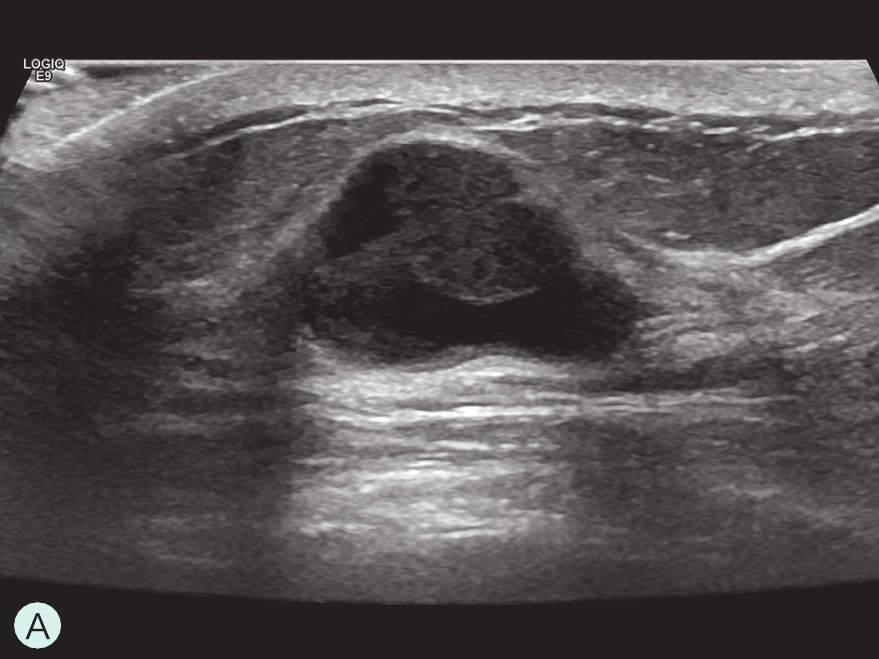

图2-2-1 确定造影病灶

A.病灶二维图像;B、C.病灶CDFI图像;D.同侧腋窝淋巴结情况;E.病灶弹性成像图像